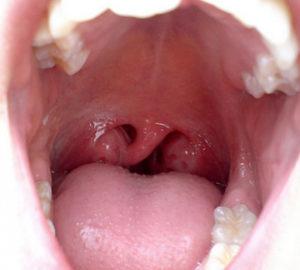

Для более точной диагностики стеноза гортани применяются различные инструментальные методы. Один из наиболее распространенных методов — это ларингоскопия, которая позволяет врачу визуально оценить состояние гортани и выявить наличие сужений, опухолей или воспалительных процессов. Ларингоскопия может быть выполнена как с использованием гибкого, так и жесткого инструмента, в зависимости от клинической ситуации.